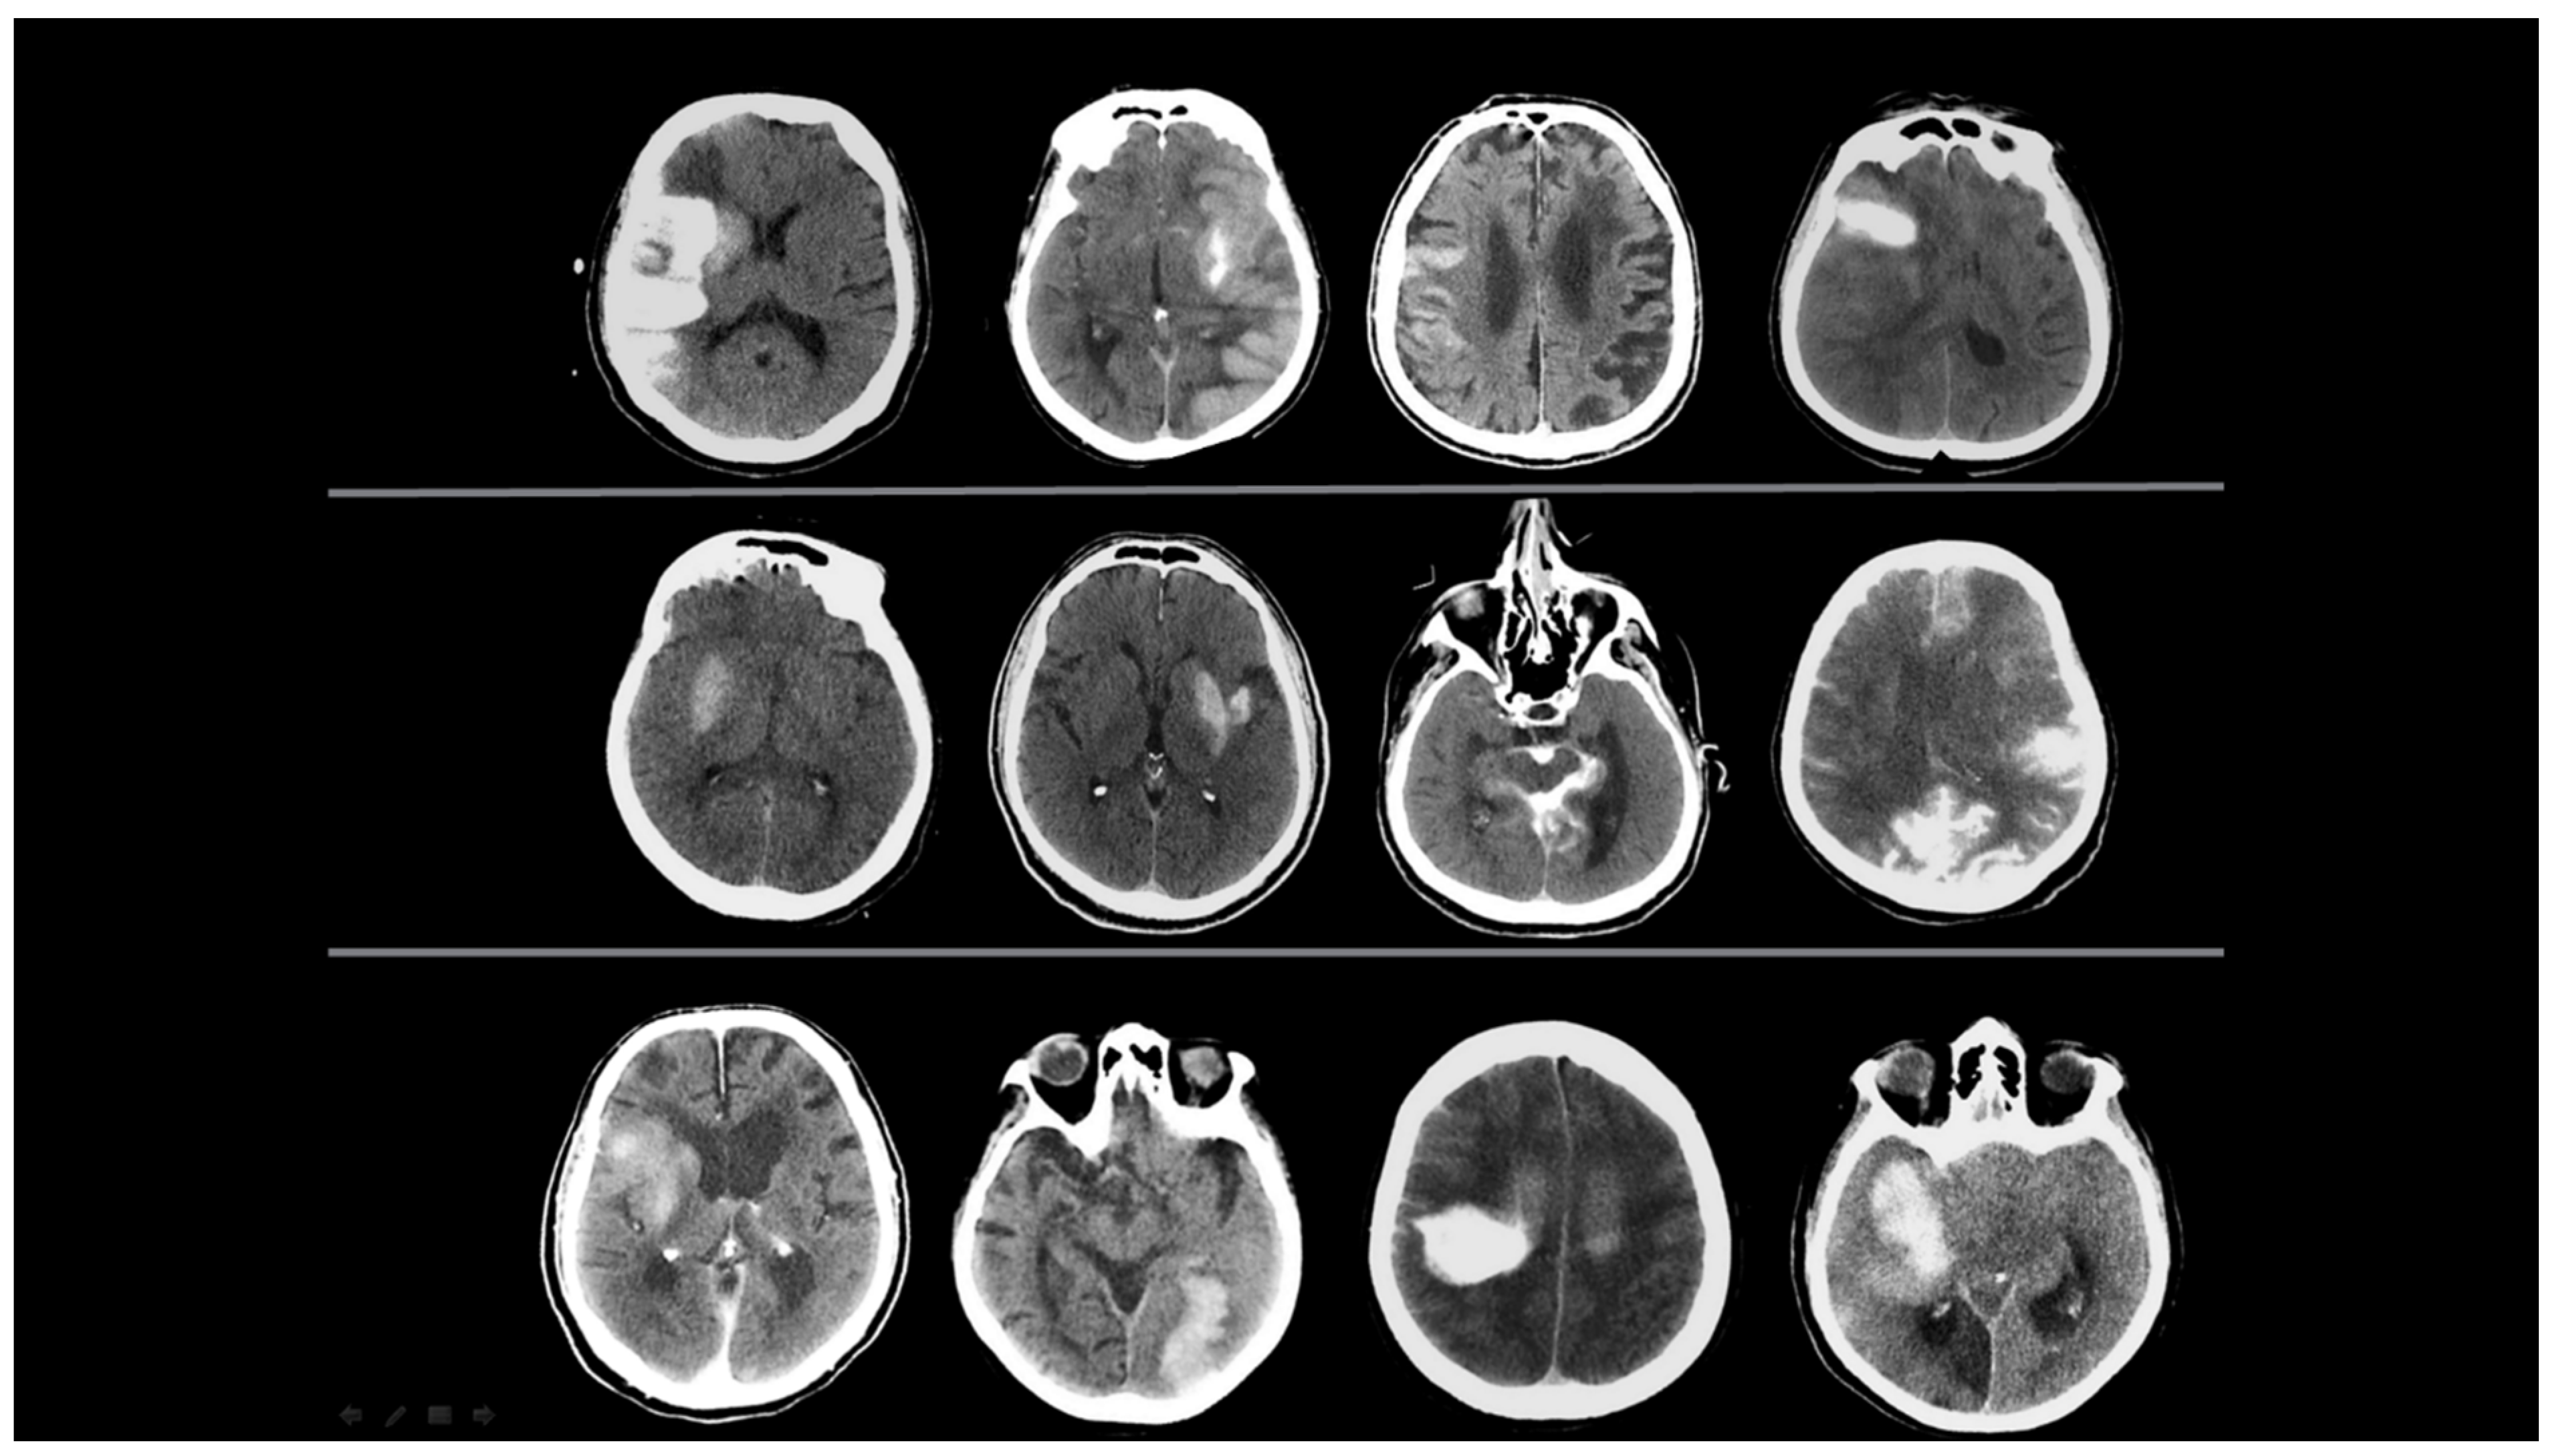

- Contrast Accumulation: The first scan found in the NCCT and the follow-up scan in the NCCT met all of the following conditions;

- Sequential follow-up scan showed hyperdensity that completely disappeared without leaving a hematoma area.

- Sequential follow-up scans show no newly developed hyperdense area.

- In sequential follow-up scans, hyperdensity that gradually decreases and completely disappears in NCCT images after 72 h.

- Hemorrhagic Transformation: The initial scan shows NCCT, and the follow-up scan shows NCCT meeting any of the following conditions.

- Hyperdensity that does not decrease or remains constant.

- Increase in hyperdensity size.